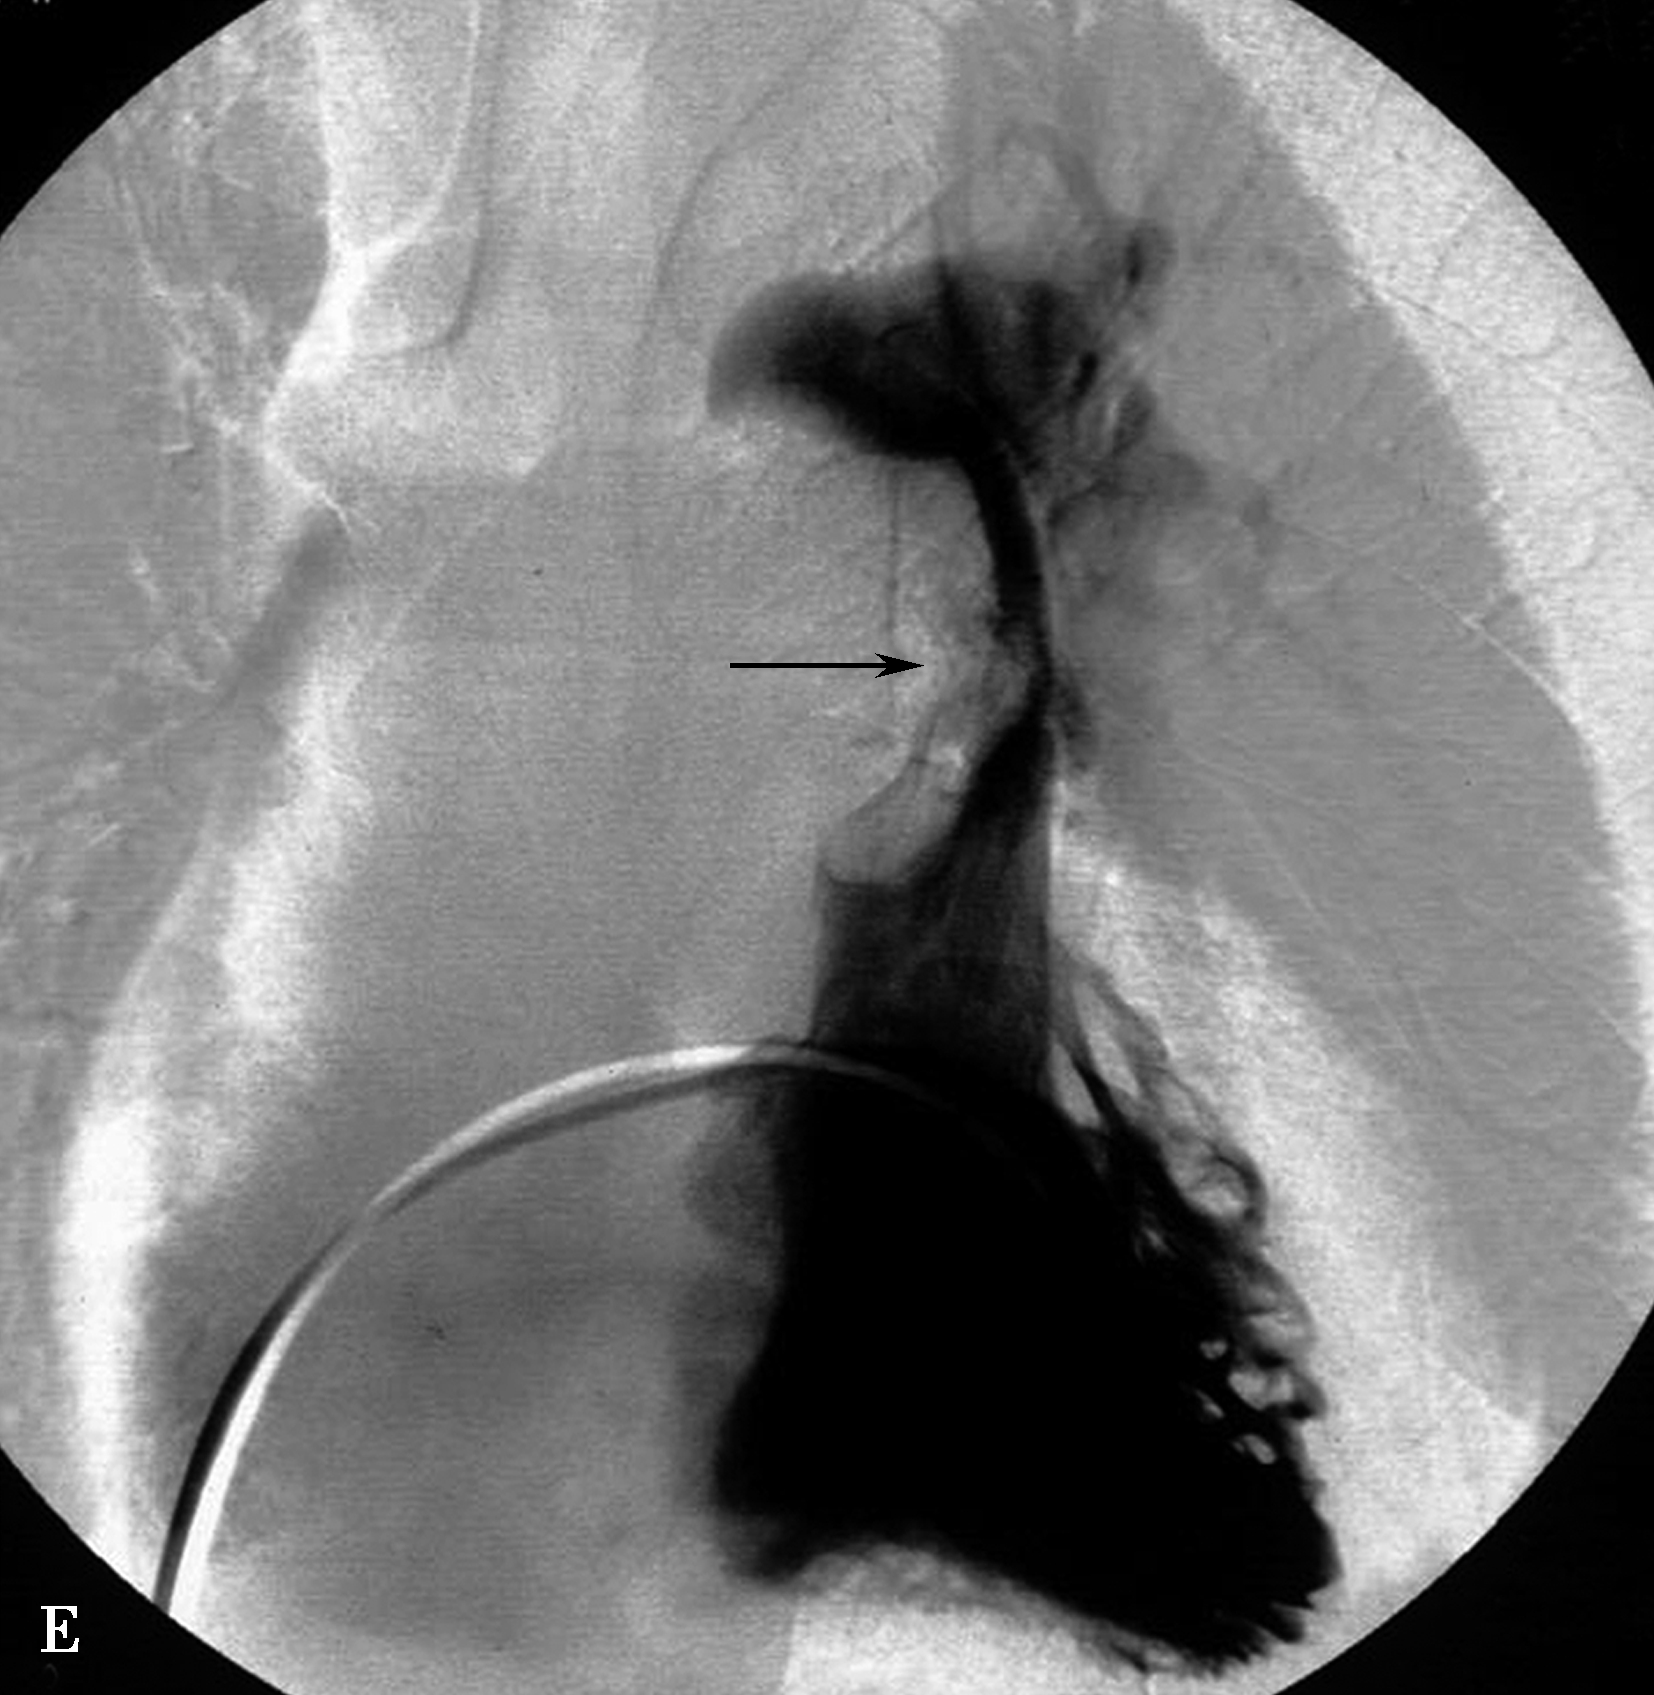

图8-7-1 女,21岁,反复咯血2年,胸闷气短1年半

CT横断扫描。A、B.多层重组;C、D.示主肺动脉及左右肺动脉内结节状充盈缺损,可见 “指压征”(↑),右肺动脉及左下肺动脉闭塞;前上纵隔中等密度影,考虑为纵隔转移(A▲)。肺动脉造影(E)示主肺动脉不规则充盈缺损,右肺动脉及左下肺动脉闭塞,术后病理诊断:低分化平滑肌肉瘤(F)

图8-7-2 男,44岁,因劳力性胸闷、气短2年余,加重1个月并出现双下肢水肿急诊入院

CT横断扫描ABCD示主肺动脉、右肺动脉干内巨大充盈缺损,膨胀性生长,累及右心室流出道(↑),主肺动脉明显扩张。肺动脉造影E,示主肺、左右肺动脉干及右下肺动脉管腔内充盈缺损(↑),两肺、左肺舌叶及下叶各基底支仅见稀疏肺动脉分支显影。病理诊断为恶性间叶细胞瘤。